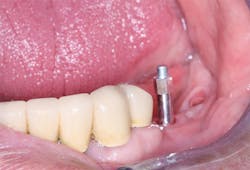

Figure 3: What resistance will this osteotomy provide to implant placement? Assuming the clinician has set the torque of the implant placement motor correctly, and the implant goes into the bone with the amount of torque at which the motor is set, the clinician may make a good estimation about the timing for implant loading.

Figure 4: On screwing the implant into place, bone density or lack of it is obvious.